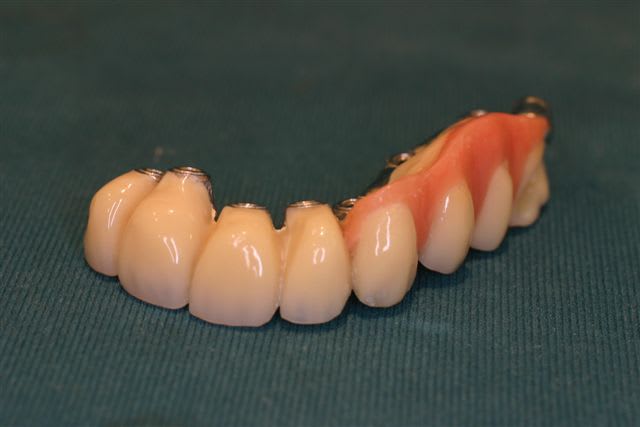

Perte d un greffon iliaque

Retraité en basale voici 6 ans avec succès